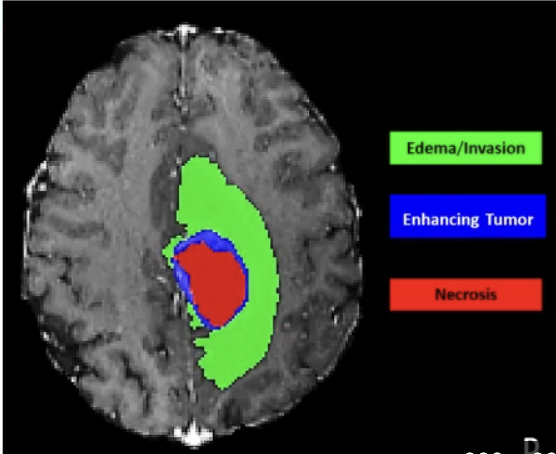

MedVLM-LoRA MedVLM-LoRA: Parameter-Efficient Brain Tumor Segmentation with Vision-Language Models Link

Designed a novel medical image segmentation framework that adapts pretrained Vision-Language Models (VLMs) to MRI data using Low-Rank Adaptation (LoRA), achieving domain transfer without full re-training. Integrated a dual-branch global–local architecture where global features capture anatomical structure while local features specialize in tumor sub-regions (edema, non-enhancing, enhancing core). Implemented a lightweight cross-attention fusion module and evaluated on the BraTS dataset to demonstrate improved tumor boundary detection, reduced trainable parameters, and lower memory footprint compared to full fine-tuning and U-Net baselines.